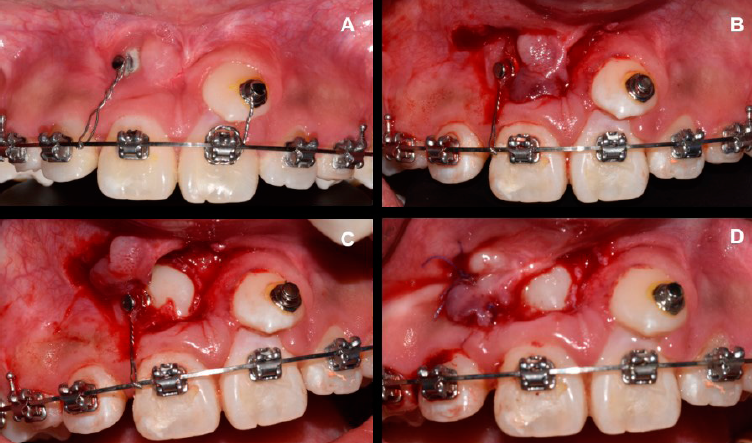

Se optó por realizar un colgajo de reposición apical para preservar la mayor cantidad de tejido queratinizado posible8 y por la posición apical del canino con respecto a la línea mucogingival. En el procedimiento quirúrgico se diseñó un colgajo de espesor parcial, se expusieron dos tercios coronales de la corona y se adhirió el botón de ortodoncia (Borgatta®) lo más cerca al borde incisal mediante sistema adhesivo 3M®. Después se reposicionó el colgajo apicalmente y se suturó al periostio con puntos simples y sutura de ácido poliglicólico 6-0, de manera que cubriera de 2 a 3 mm de la corona (Figura 1. A-D).

Figura 1 Técnica de cirugía plástica periodontal para la exposición del diente 13. Caso1. A. Diseño de un colgajo espesor parcial que se reposicionará apicalmente. B. Exposición del diente 13. C. Colocación del botón de ortodoncia. D. Reposición apical del colgajo a partir de puntos simples y sutura de ácido poliglicólico 6-0.

La tracción del diente 13 se activó en el momento de la colocación del botón ortodóncico con una cadena elástica de segunda generación cerrada Ormco®, en dirección al diente 14, para guiar la erupción (Figura 1. C-D). La tracción se llevó a cabo de manera intermitente desde la exposición del diente hasta el noveno mes de seguimiento ortodóncico donde se logró posicionar al diente con fuerzas ligeras y continuas al año posquirúrgico.